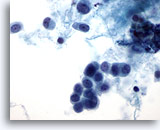

Figure 48

Breast FNA, Lobular carcinoma.

The neoplastic cells are usually small, with round to irregular nuclear margins and eccentric nuclei, producing a plasmacytoid appearance as illustrated in this field. 60x

Figure 48

Breast FNA, Lobular carcinoma.

The neoplastic cells are usually small, with round to irregular nuclear margins and eccentric nuclei, producing a plasmacytoid appearance as illustrated in this field.

60x